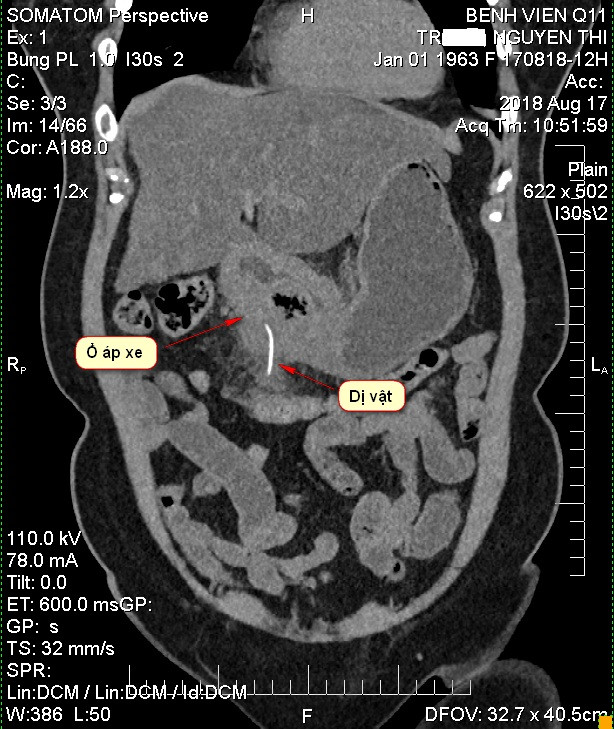

Bệnh nhân suýt chết vì xương cá dài 5cm đâm thủng dạ dày ảnh 1Chiếc xương cá dài 5cm đâm thủng dạ dày bệnh nhân

Sau khi thực hiện các kỹ thuật cận lâm sàng, các bác sĩ phát hiệ một tổn thương khu trú, có dị vật cản quang trong thành dạ dày vùng môn vị nên nghi ngờ dị vật có thể bằng kim loại.

Sau khi hội chẩn, bệnh nhân nhanh chóng được bác sĩ chỉ định thực hiện phẫu thuật cấp cứu. Sau khi mở bụng, tiến hành thám sát nhận thấy xương cá dài 5cm trong dạ dày nên tiến hành lấy dị vật ra khỏi cơ thể bệnh nhân. Sau đó, bác sĩ tiến hành khoét bỏ ổ loét viêm đường kính 3 cm đồng thời khâu lại dạ dày. Theo các bác sĩ nếu không được phẫu thuật kịp thời ổ áp xe vỡ ra tràn vào ổ bụng sẽ gây viêm phúc mạc toàn thể dễ khiến bệnh nhân tử vong sau sốc nhiễm trùng.